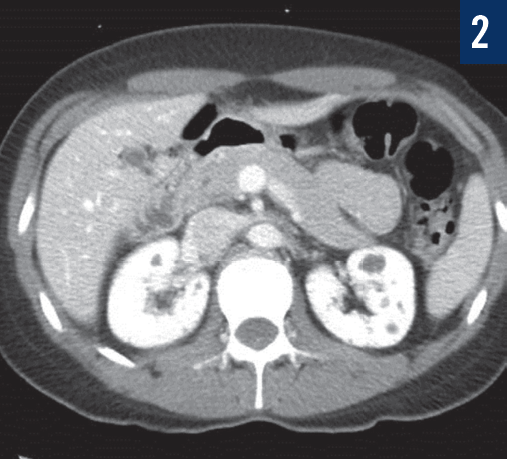

Ricky Kortyna, MMS, PA-C; Emily Murphy, MPAS, PA-C

A 36-year-old woman was seen in the emergency department secondary to the acute onset of right lower-quadrant pain.